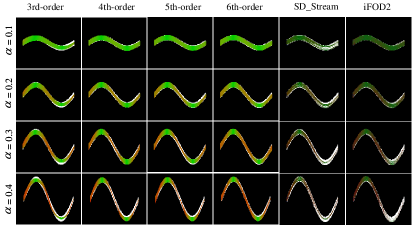

Figure 3: Comparison of tractography results of BTD with iFOD2 and SD_Stream at different SNRs using the Sine data (α=0.3𝛼0.3\alpha=0.3).

Refer to caption

Figure 4: Comparison of tractography results of BTD with iFOD2 and SD_Stream at different α𝛼\alpha using Sine data (SNR=10).

To evaluate the tractograms of BTD on different orders, we test BTD from the 3rd- to 6th-order on Hough data and Sine (α=0.3𝛼0.3\alpha=0.3) data with SNRs of 10, 20, and ++\infty, which are shown in Fig. 2 and Fig. 3. We further test the algorithms on Sine data with α𝛼\alpha from 0.1, 0.2, 0.3, and 0.4 (Fig. 4) to adjust the amplitude. The quantitative results of Hough data with SNR=10, Sine data with α=0.3𝛼0.3\alpha=0.3 and SNR=10, and Sine data with α=0.4𝛼0.4\alpha=0.4 and SNR=10 are shown in Table. 1. From Fig. 2, Fig. 3 and Table. 1 show the fitting ability increase, and the BTD with 5th-order and 6th-order yield better results than the 3th-order and 4th-order BTD. Compared to the 5th-order BTD, the 6th-order BTD shows approximate fitting ability but the complexity will increase significantly because the coefficients of the BTD from the 5th-order to the 6th-order will increase by 84 terms. Therefore, the 5th-order BTD is used to compare the tractography results in the following experiments. Notion, we can select the lower order of BTD when we track the simple bundles, which can reduce running time. However, for the complex bundle, like the corpus callosum, we suggested the higher order of BTD as the bundle is complex. Moreover, for most of the bundle in vivo, the fitting ability of 5th-order is sufficient and the run time is suitable. Therefore, we recommended the 5th-order of BTD for some complex bundles.

We compare the tractograms among 5th-order BTD, SD_Stream, and iFOD2. From Fig. 2, the tractograms of BTD are evenly distributed in the mask and have larger VC and OL than SD_Stream and iFOD2 with different SNRs. In addition, the tractograms of SD_Stream and iFOD2 show the small angle of divergence, and fewer fibers reach the large fanning regions on Hough data. As an important factor affecting tractography, error accumulation leads to premature termination of the fibers, which is more obvious in long-range and large twisting connections, such as the bundle on Sine data (Fig. 3). The BTD obtains larger spatial coverage as well as better VC and OL at different SNRs. To further compare the tractograms on more complex data, we adjust the from 0.1, 0.2, 0.3, and 0.4 for Sine data (Fig. 4). The BTD shows more stable tractograms and higher VC and OL, while SD_Stream and iFOD2 exhibit an increase in the number of prematurely terminated fibers with decreasing amplitude. In Fig. 5, the BTD shows less deviation with increasing noise and most of fibers can return their starting points. In Fig. 6 and Table. 3, the BTD shows better performance compared with SD_Stream and iFOD2, specifically for the bundles with crossing and fanning (E1-E2, E1-E4). The BTD shows large VC and OL and lower OR compared with SD_Stream and iFOD2. Additionally, the computational time from 3th- to 6th-order BTD may be need approximately 2.0s, 2.4s, 5.8s and 9.2s runtime using Hough data (repeat 100 times; in fourth column in Table. 1) with Inter i-9900k processor and Matlab2019 platform.